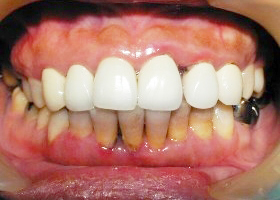

5. 矯正後,上顎外暴及下顎參差不齊的情況大幅改善。

proimages/case/cosmetic/pic_case-026.jpg

proimages/case/cosmetic/pic_case-027.jpg